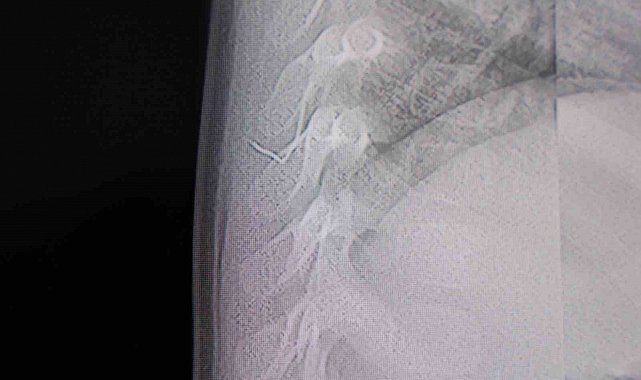

Alınan bilgiye göre, Kahramanmaraş'ta farklı ortopedi, çocuk cerrahisi ve beyin cerrahisi kliniklerine başvurusu yapılan bir yaşındaki bebeğin, sırt bölgesinde yabancı bir cisim olduğu ancak müdahalenin zor olduğu ve 8 yaşına kadar beklenmesi gerektiği bildirildi. Aile, bebekleri için son olarak HG Hospital'e başvurdu. HG Hospital Beyin ve Sinir Cerrahisi Uzmanı Prof. Dr. İdris Altun tarafından yapılan tetkiklerde, yabancı cismin cilt altında, omurilik kanalına yakın bir bölgede olduğu ve akciğer zarına doğru ilerlediği belirlendi. Hasta, genel anesteziye alınmadan, lokal anestezi ve sedasyon eşliğinde ameliyata alındı. Yapılan müdahalede yabancı cisim tamamen çıkarıldı. Çıkarılan cismin, ince zımba teline benzer metal bir tel olduğu ve yaklaşık 2 santimetre uzunluğunda bulunduğu tespit edildi. Hasta, aynı gün taburcu edildi.

Konuya ilişkin açıklama yapan Prof. Dr. İdris Altun, "Sırtında yabancı bir cisim olduğu söylenmiş ancak çıkarılamayacağı ve 8 yaşına kadar beklenmesi gerektiği ifade edilmişti. Bize başvurduğunda yaptığımız tetkiklerde, cilt altında, omurilik kanalına çok yakın ve akciğer zarına doğru ilerleyen bir yabancı cisim tespit ettik. Hastamızı tamamen uyutmadan, lokal anestezi ve sedasyon eşliğinde müdahale ederek lezyonu tamamen çıkardık. Çıkardığımız cismin ince zımba teline benzer, yaklaşık 2 santimetre uzunluğunda metal bir tel olduğunu gördük. Bu yabancı cisim alınmasaydı, bölgede enfeksiyon gelişebilirdi. Enfeksiyon sonucu omurilik kanalında ciddi hasarlar oluşabilir, çocuk büyüdükçe cismin hareket etmesine bağlı olarak omurilikte zedelenmeler meydana gelebilirdi. Ayrıca yana doğru ilerleyerek akciğer zarına ve akciğere batma riski vardı. Bu da enfeksiyona ve ilerleyen süreçte tümörle karışabilecek tablolara neden olabilirdi. Şu an hastamız gayet sağlıklı. Gerekli kontrolleri yaptık ve aynı gün taburcu ettik" dedi.